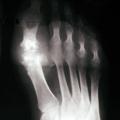

La forme pseudorhumatoïde est rare (5 %), simulant une polyarthrite rhumatoïde (diagnostic différentiel), avec parfois des signes systémiques d’inflammation (élévation de la vitesse de sédimentation et de la CRP). Le diagnostic repose sur la mise en évidence des cristaux de PPC. La radio peut mettre en évidence des calcifications des cartilages articulaires (fig. 6) et des fibrocartilages (fig. 7, 8, 9 et 10). L’échographie (plus sensible) peut mettre en évidence des dépôts de PPC, qui apparaissent comme une fine bande hyperéchogène au sein des cartilages hyalins et comme des points scintillants dans les fibrocartilages ou dans la membrane synoviale. Dans l’arthrite chronique à PPC, lespossibilités thérapeutiques sont, par ordre de préférence : colchicine (de 0,5 à 1 mg/j), petites doses de cortisone, parfois les AINS per os (mais leur prescription est souvent limitée par les comorbidités chez les patients âgés), méthotrexate et l’hydroxychloroquine. Il n’y a pas aujourd’hui de traitement « de fond », mais des molécules sont à l’étude.